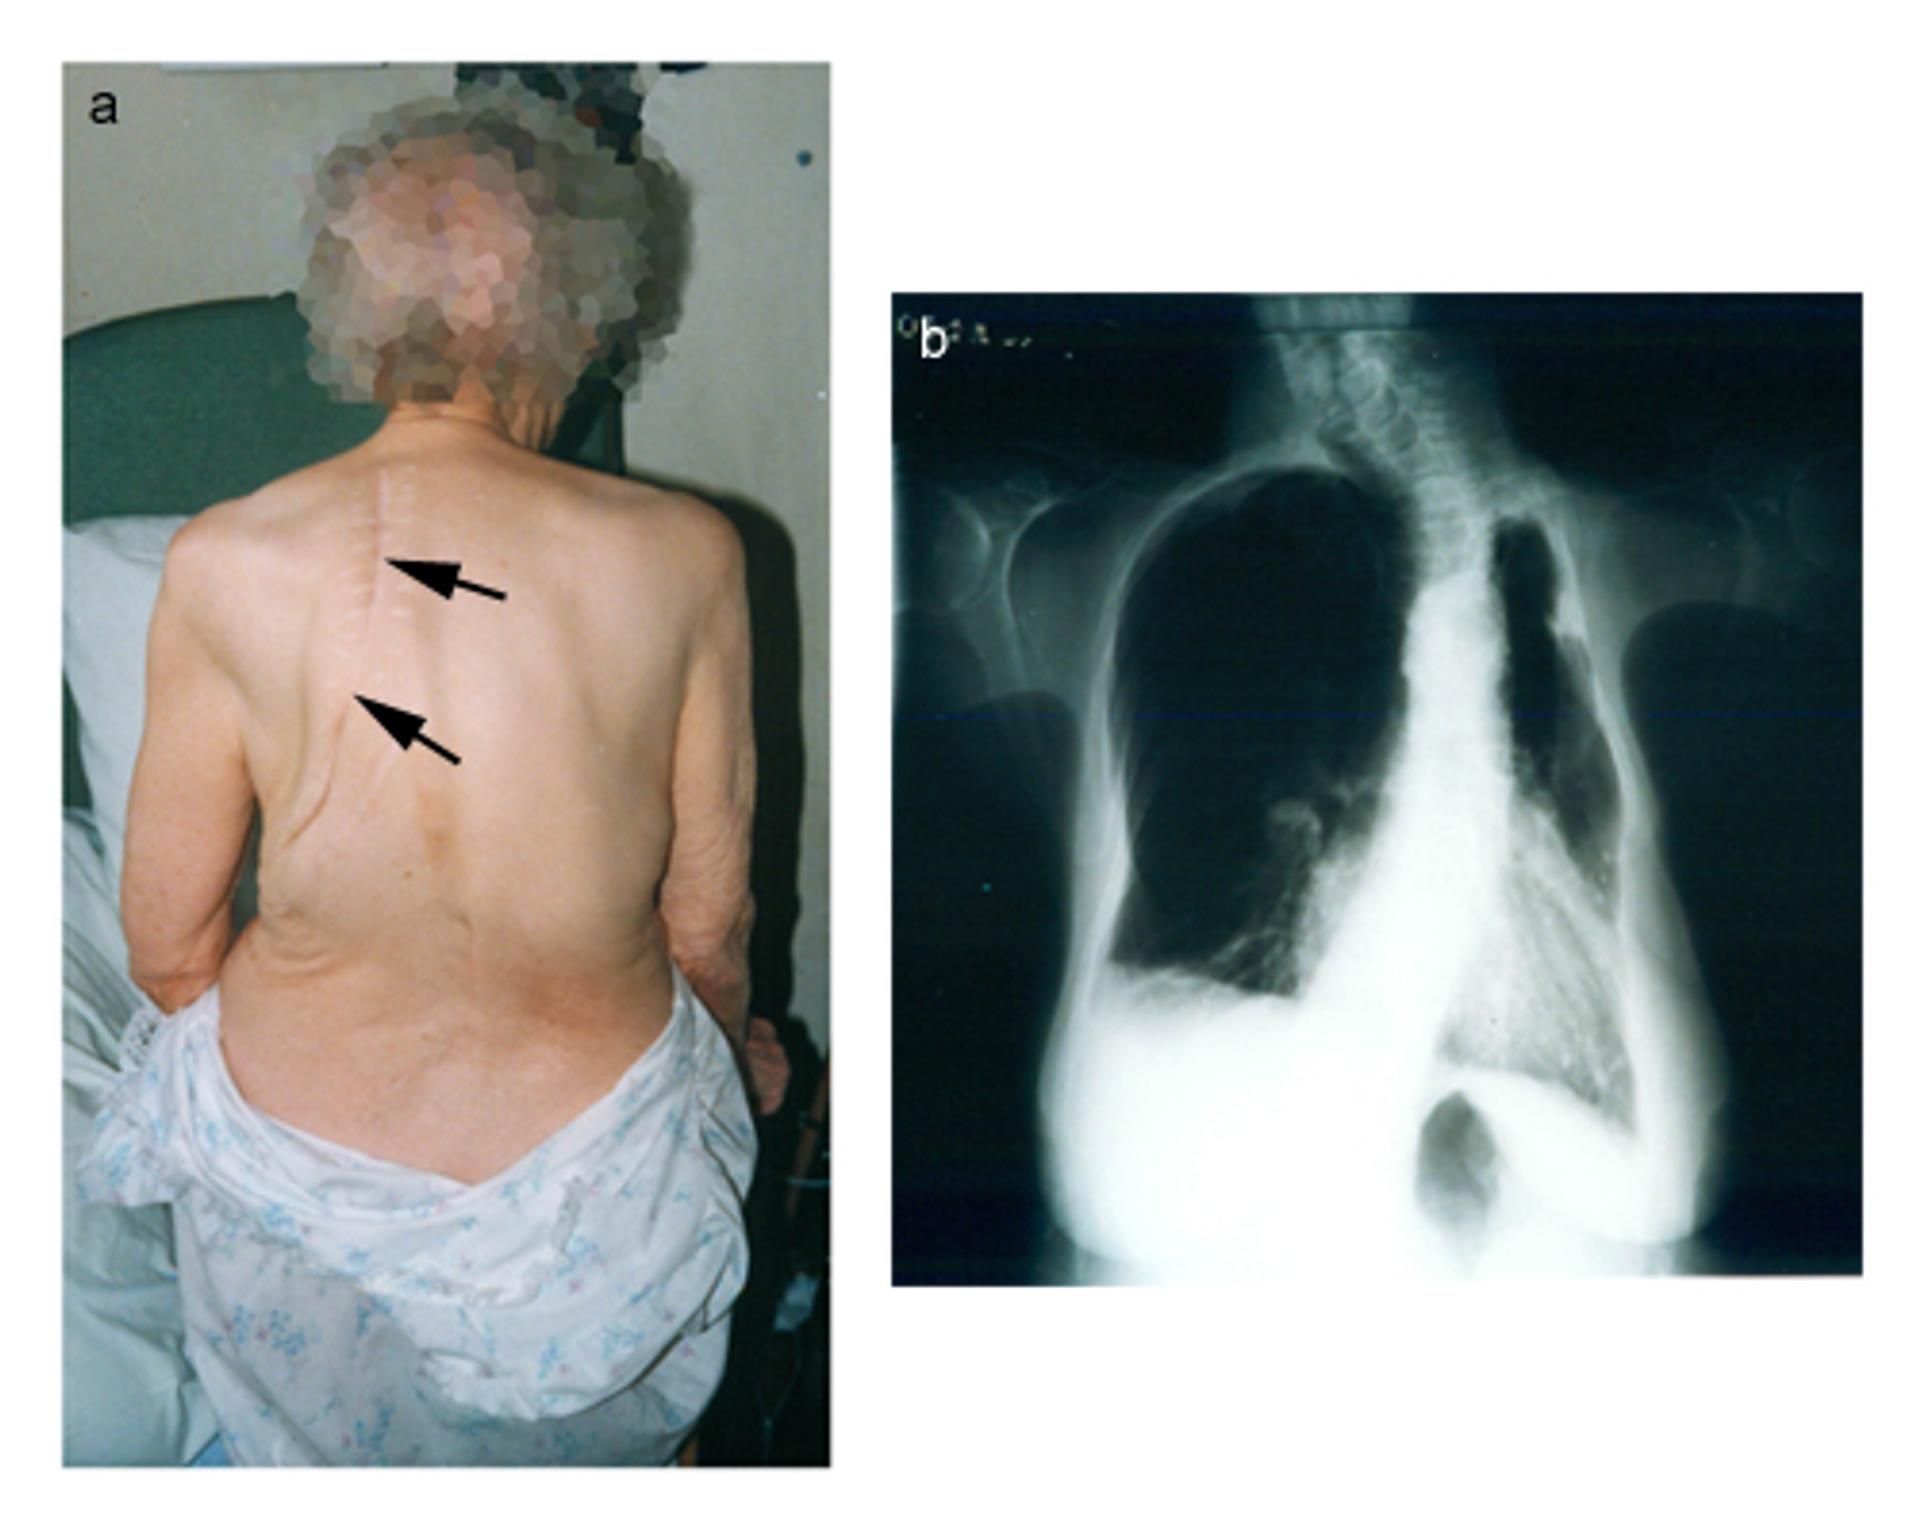

Photograph of thoracoplasty for TB

a) photograph from the rear showing loss of volume in the chest on the left side with thoracoplasty scar (arrows)

b) radiograph showing loss of volume on the left